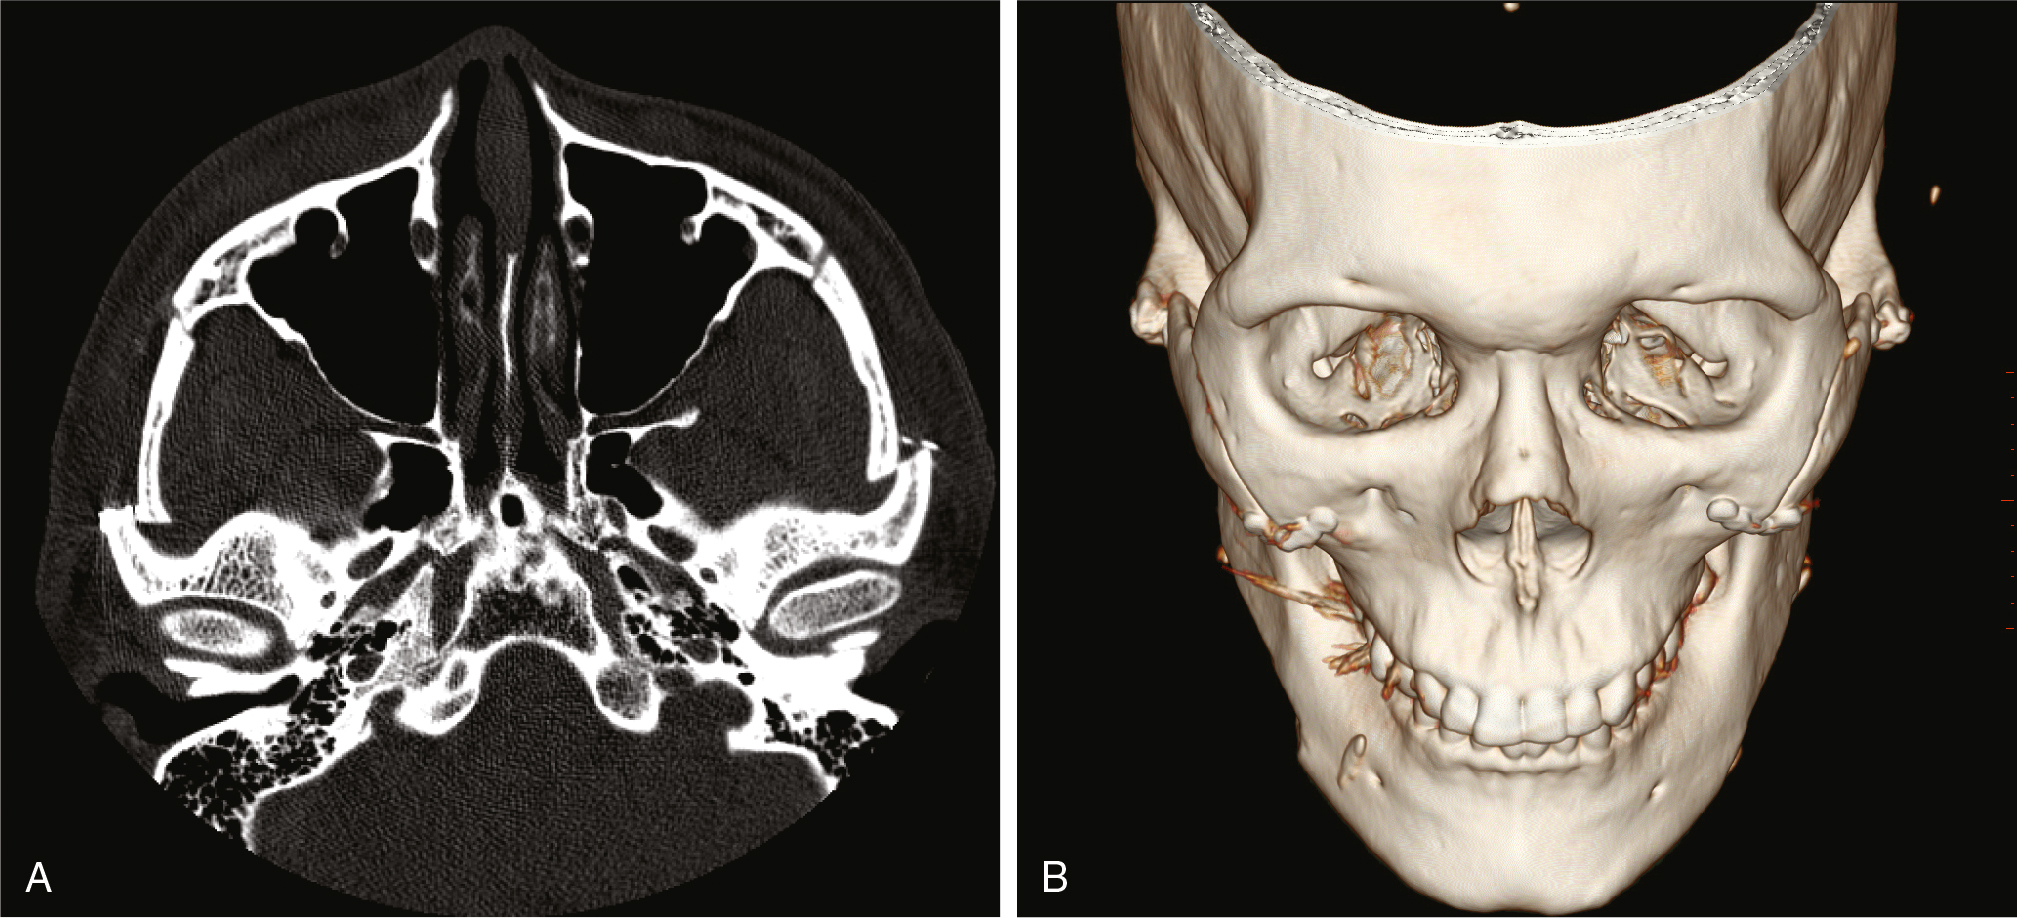

At a minimum, preoperative imaging should include radiographs and 2D photographs of the patient’s face. Ideally, 3D computed tomography (CT) or cone beam computed tomography (CBCT) will be available to review and to rule out the presence of any bone pathology and to visualize relevant anatomy, such as the inferior alveolar canal. Virtual surgical planning (VSP) is useful, and as the soft tissue responses to bone movements are quantified, VSP may play a more critical role in predicting the final outcome of the planned osteotomies.